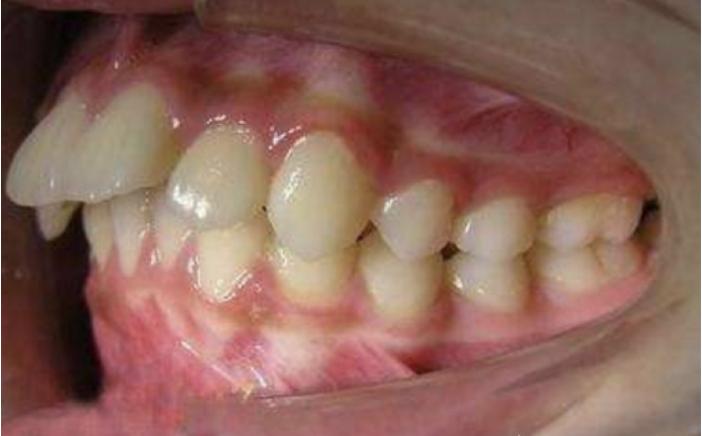

牙齿“飞出去”造成龅牙

牙齿直立,牙槽骨凸出造成的龅牙